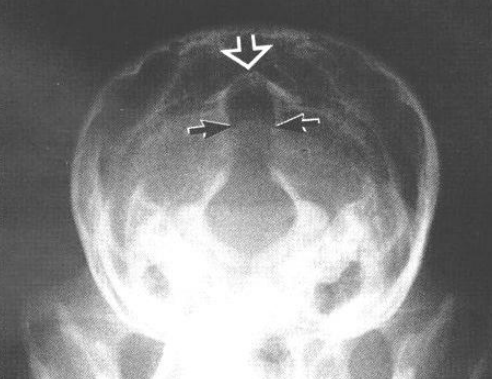

방사선 소견

- 두개관의 확장, 두개골 피막 변화

- 두개골 골봉합선 결여

- 뇌실 음영이 균질함

- latearal ventricle에 물이 차서 mottling sign이 보이지 않고, soft density가 높아짐

- 배측 후두골의 경계소실 : keyhole sign

- 전두골후두골(fronto-occipital view) 방향 촬영에서 잘 관찰됨.

- 연부조직밀도가 생김.